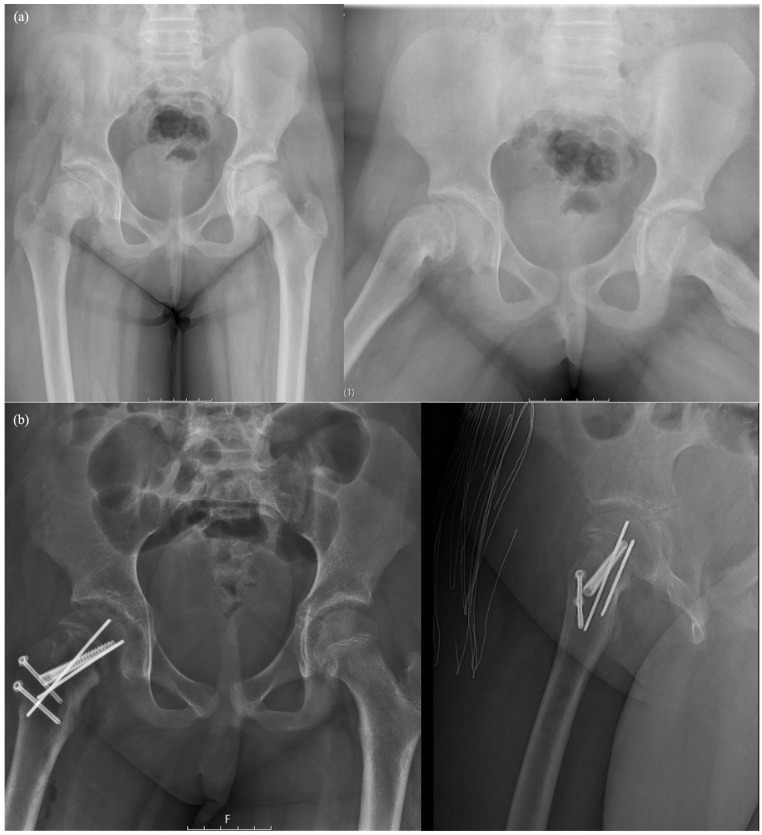

Purpose: The study aimed to compare the clinical and radiologic results of in situ pinning and modified Dunn procedure methods in stable-moderate slipped capital femoral epiphyses surgery.

Methods: Slipped capital femoral epiphyses cases between January 2000 and December 2022 were retrospectively analyzed. Stable and moderate cases treated with in situ pinning or modified Dunn procedure and those with a follow-up period longer than 1 year were included. Two groups were formed: the in situ pinning group and the modified Dunn procedure group. Radiologically, postoperative alpha angle, Southwick angle, avascular necrosis, and osteoarthritis rates were compared. Clinically, Harris Hip Score and Merle d'Aubigné score were compared. Total complications were evaluated.

Results: The in situ pinning group consisted of 28 patients and the modified Dunn procedure group consisted of 17 patients. The groups were similar in terms of age, gender, affected side, body mass index, Fahey/O'Brien Classification, preoperative slip angles, and follow-up time. Operation time was shorter in the in situ pinning group (p < 0.001). Postoperative Southwick and alpha angle were lower in the modified Dunn procedure group (p < 0.001). In clinical outcomes, Merle d'Aubigné and Harris Hip Score were higher in the in situ pinning group (p = 0.013, p = 0.005, respectively). The rate of avascular necrosis was higher in the modified Dunn procedure group (p = 0.048). There was no difference between the groups in terms of total complications and osteoarthritis.

Conclusions: In situ pinning has an advantage over the modified Dunn procedure in the treatment of stable-moderate slipped capital femoral epiphyses due to shorter operative time, better clinical outcomes, and fewer avascular necrosis rates. Although Southwick and alpha angle measurements were found to be higher after in situ pinning compared to the modified Dunn procedure, this does not constitute a significant disadvantage in terms of osteoarthritis development in the mid-term.